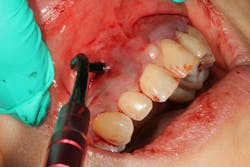

PRF is an autogenous biomaterial derived from the patient’s blood. It is rich in growth factors and cytokines that accelerate tissue repair, angiogenesis, and wound healing. When combined with PST, PRF acts as a natural scaffold, promoting soft-tissue healing, maintaining tissue volume, and potentially reducing gingival inflammation. PRF’s bioactive properties allow for improved attachment of gingival tissues and greater stability in areas of multiadjacent recession (figures 3–5).

Recent advancements in combining PRF (i.e., Bio-PRF) with PST have shown increased effectiveness in root coverage, enhanced gingival thickness, and better postoperative outcomes when compared to PST alone (figure 6).